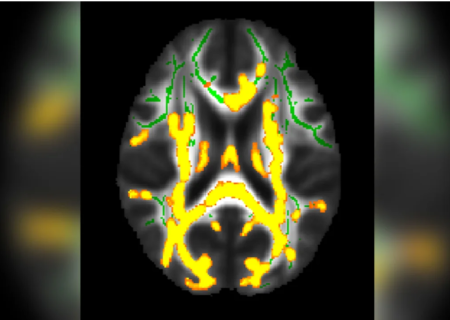

آلزایمر

مطالعه محققان در باره تاثیر پروتئین ها در رابطه با زوال عقل

ارتباط چربی پنهان شکم با التهاب مغز و زوال عقل

بر اساس مطالعه، افراد 40 و 50 ساله با مقدار بیشتری چربی پنهان شکم «مقدار بیشتری از پروتئین غیرطبیعی به نام آمیلوئید در بخشی از مغز دارند که یکی از اولین مکانهایی ست که آلزایمر در آن رخ میدهد.